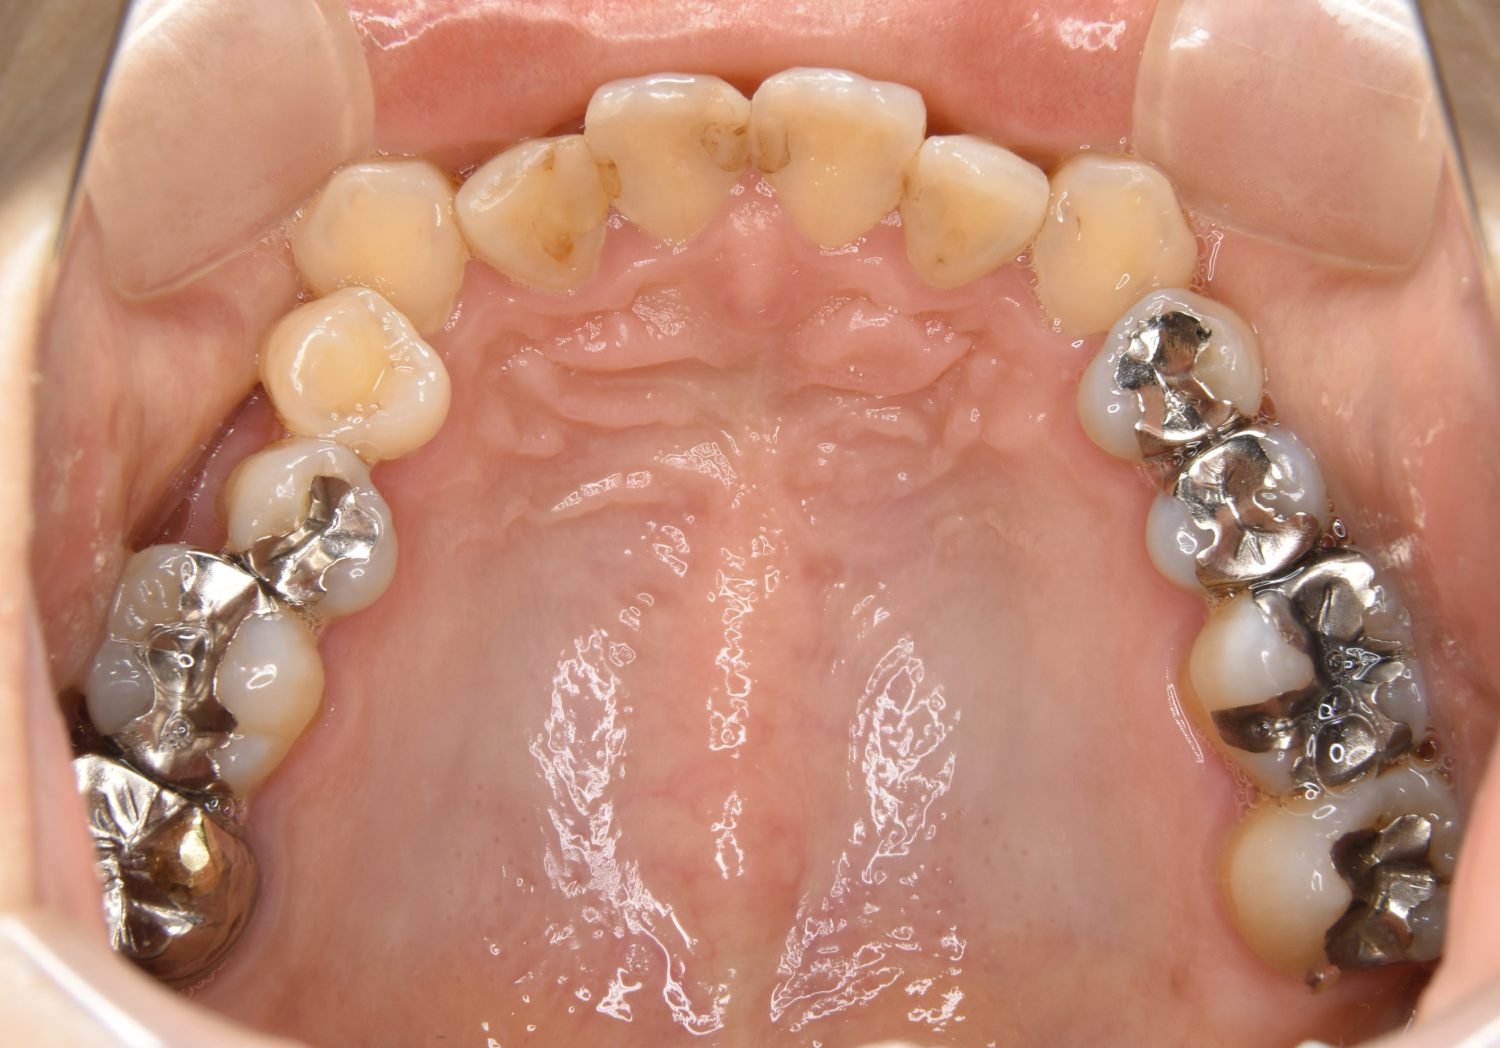

Before

主訴

前歯のガタガタが気になる。

治療内容

上顎左側第一小臼歯を抜歯し、アライナー(インビザライン)にて治療を行いました。

左上の側切歯が完全に内側に入り込んでいる状態でした。左上の第一小臼歯のみ抜歯を行い治療を行うことで機能面および審美面を改善しました。